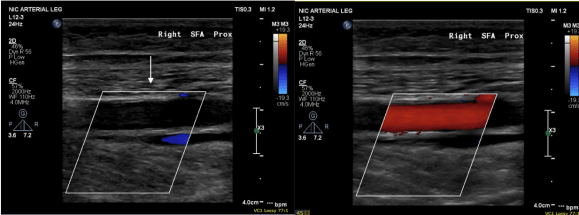

The hardest case that I have taken care of ever was at the Clinic a couple of years ago. The patient was a middle aged man who had ruptured an aortic aneurysm in another state some months prior and had undergone a repair complicated by a pancreatic injury along with some enterotomies resulting in a graft infection along with high output pancreatic and enteric fistulae from an open abdomen. He arrived cachectic, in septic shock and had a pseudoaneurysm from the distal anastomosis of a short tube graft. I immediately took him to the OR to place a stent graft across the pseudoaneurysm neck to prevent rupture and placed him on TPN to correct his cachexia. The abscesses and hematomata were drained percutaneously, and an effort was made to control the fistula with a heroic effort on the part of the ostomy team. He turned around and was able go to an LTAC on TPN and antibiotics. There he gained twenty pounds and returned flush and active. Stage two was three months later and done to replace the still infected grafts with cryopreserved homograft. I did this via a right retroperitoneal approach as the left side and abdomen were a mess from the inflammation. After I removed the grafts and sewed in the homograft, general surgery reorganized his bowel and discovered that he only had about 30cm of useable small bowel and would be on TPN for life. But he was alive and learning to walk again, and eventually came back 6 months later for follow-up and gave me a hug.

That case took all of my skill to solve, and I could not have done it without the whole hospital working in sync with me. When it comes my time, I wonder who would be able to do that for me?Who would manage my ruptured AAA properly and not have bowel and pancreatic injuries?